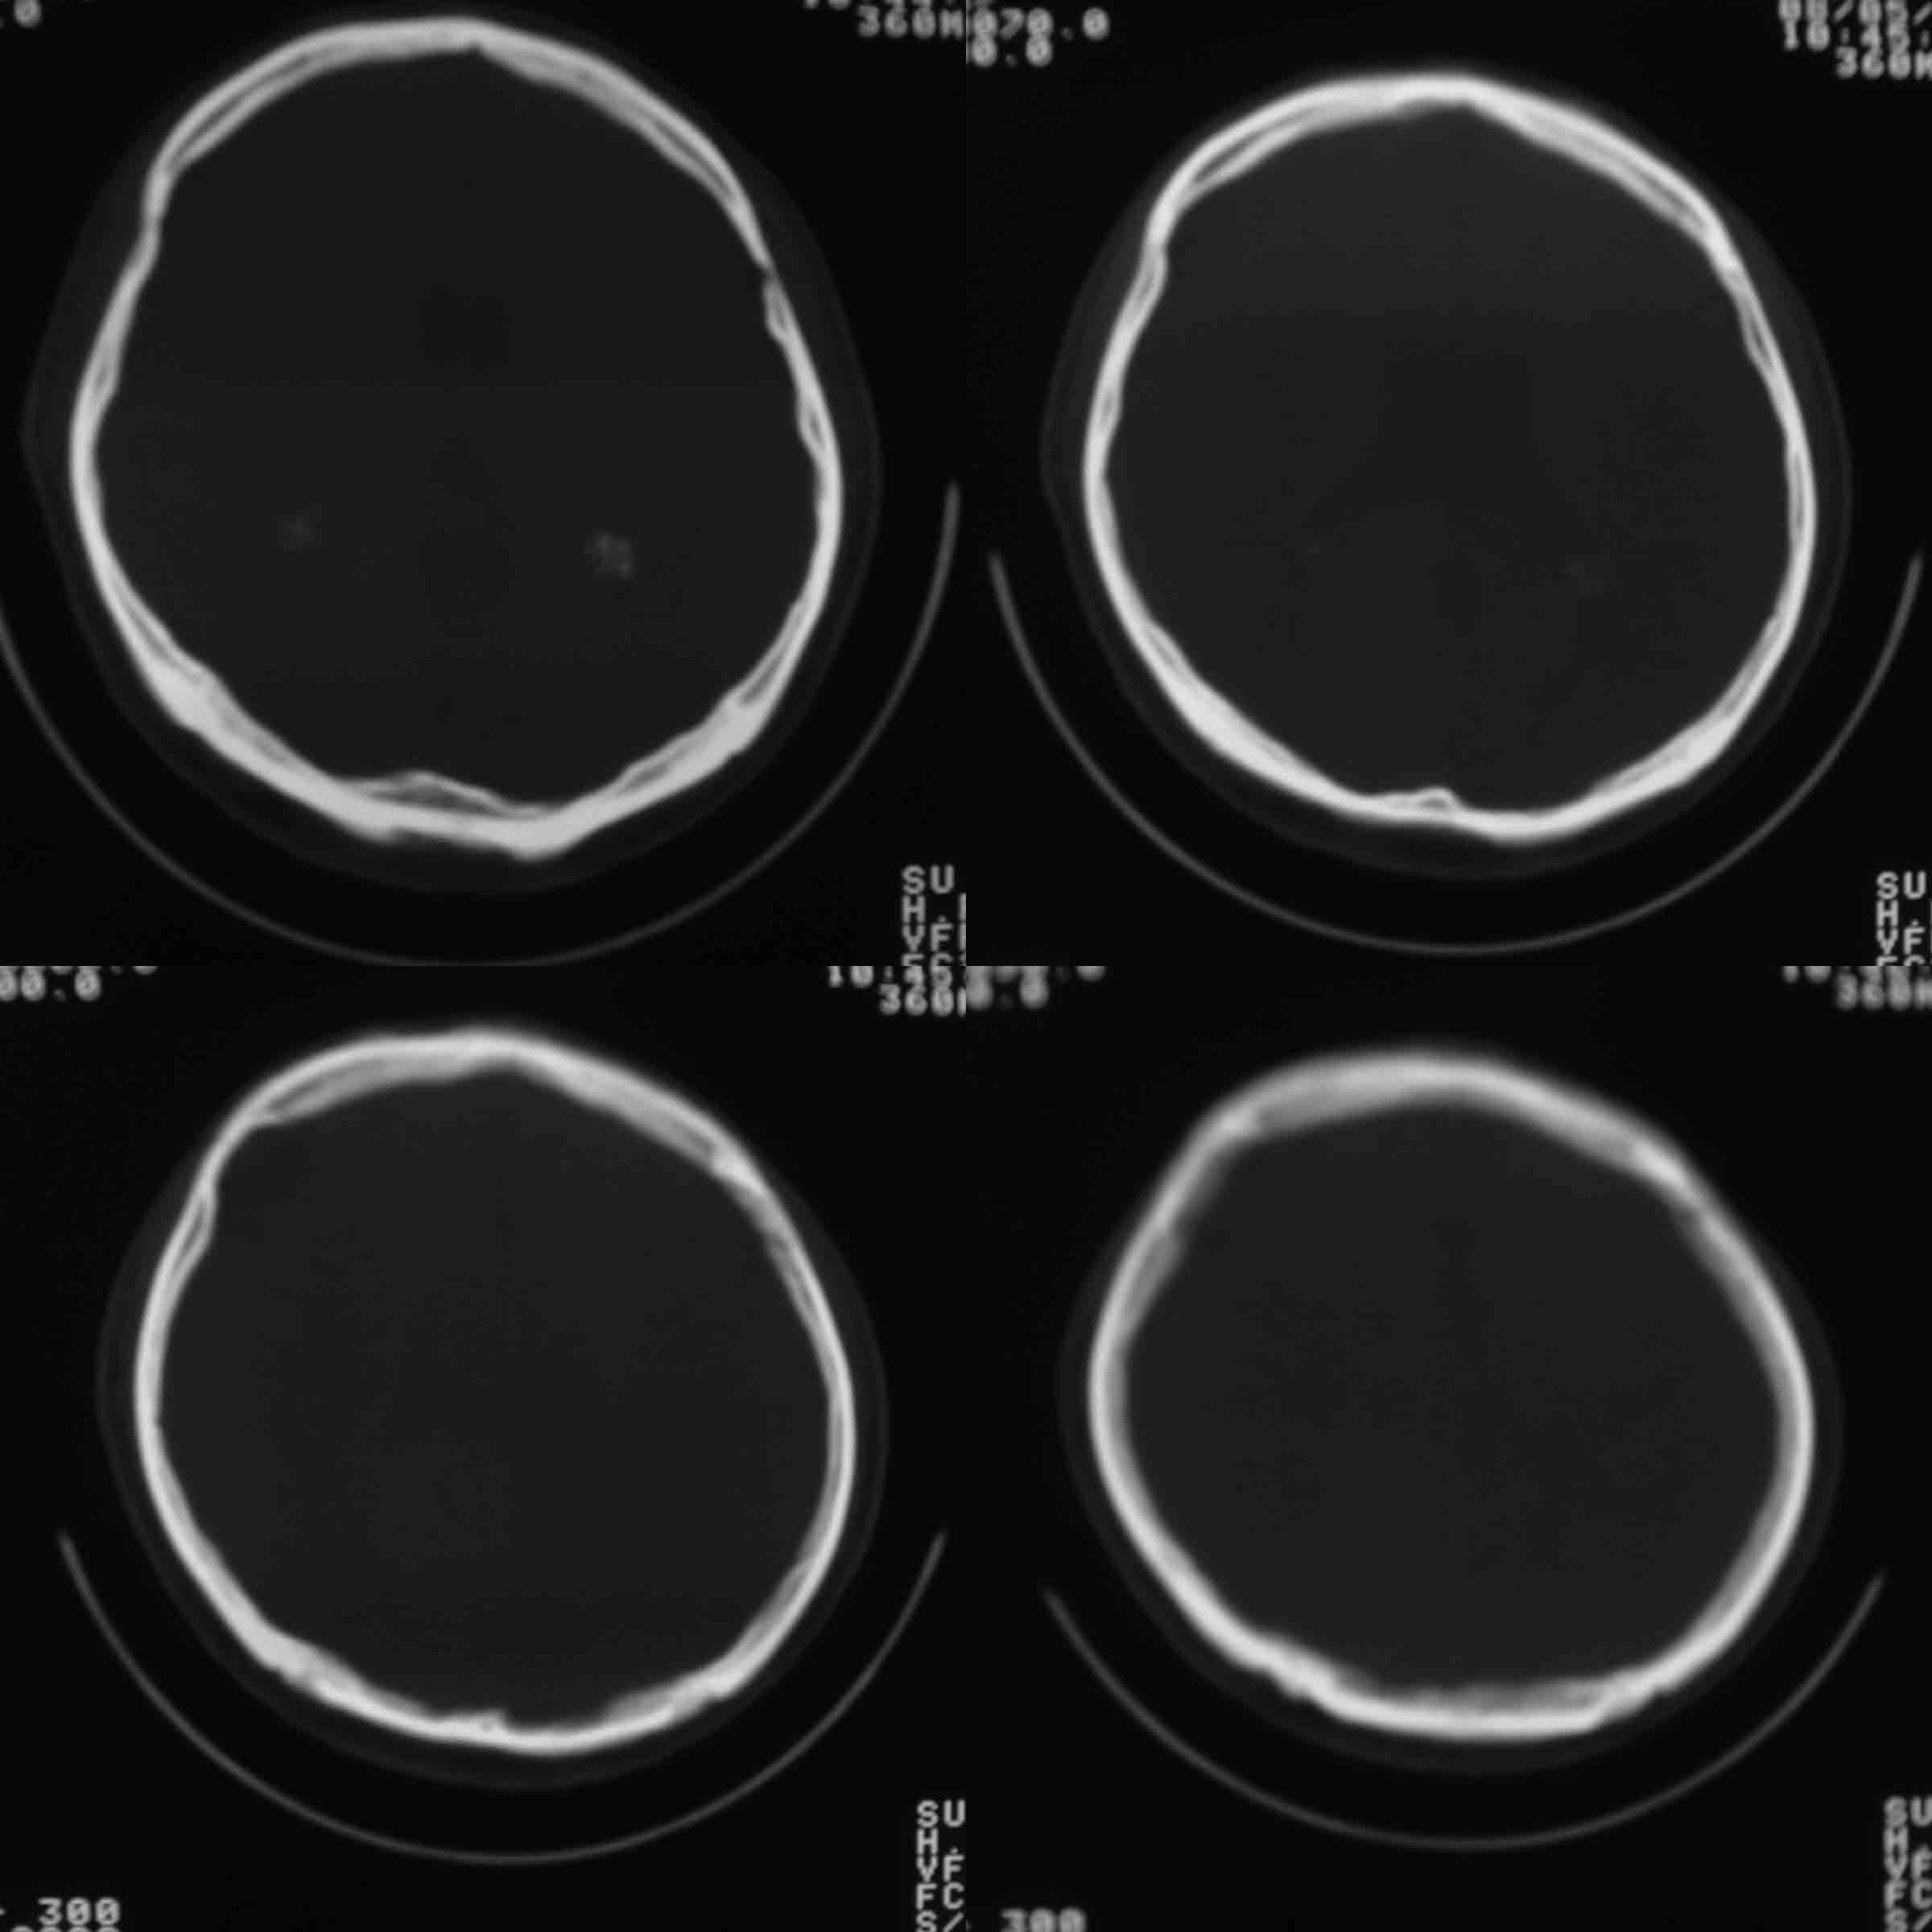

男37岁头持续性痛1天。右额部蛛网膜下腔囊肿诊断是否正确,请老师们帮忙看看。谢谢!

支持右额区蛛网膜囊肿。

有顶叶蛛网膜下腔囊肿

右侧额叶蛛网膜囊肿。